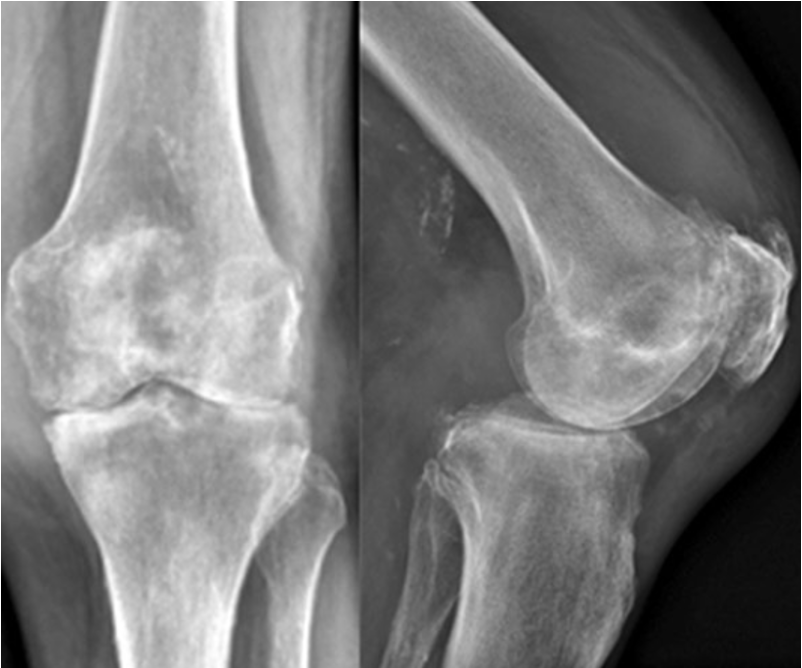

Full history should include pain and function before infection, cause of infection, all conservative and surgical therapies, microorganism, AB therapy as well as profession, sporting activities and expectations. Clinical examination should include skin, swelling, ROM, stability, and extensor mechanism function. Standard radiographs including special views, MRI and CT are summarized in table 1. Lab tests to exclude high risk factors and confirm infection are summarized in table 2.

16 consecutive patients with active SA had been treated with a two stage TKA procedure between 2006 and 2016. Mean FU was 6.1 years (range 2.0 to 9.9 years) and no patient was lost for FU. The median number of prior open or arthroscopic debridement before the two-stage procedure was 2 (range 1 to 6). All patients showed clinical and laboratory sign of a septic arthritis with severe chondrolysis or OA. The infection was cured after 6 weeks for all knees. Final implantation was performed between 6 to 12 weeks in all patients with a varus/valgus constraint implant (NexGen LCCK, Zimmer, Warsaw). Only three knees needed a CCK insert, whereas 13 knees were stable enough for using a PS insert only. For the AB spacer and final implantation no intra- or postoperative complications occurred.

No patient needed a brace for mobilization and all patients where highly satisfied with their pain and function in the interval. They reported residual pain only, were able to walk without crutches with good ROM and many of them even ask if the final implantation will be necessary. After final implantation the patients showed comparable outcome to normal primary knees. The mean KSS objective and function score increased significantly from preop situation (58/17) to after spacer implantation (75/46) and further improved after TKA implantation at the final FU (96/86). The mean VAS score was 6.5 preop, decreased to 2.1 after the spacer and 1.2 after TKA at final FU. At final FU no clinical or radiographic signs of infection, loosening or osteolysis could be identified in all patients.